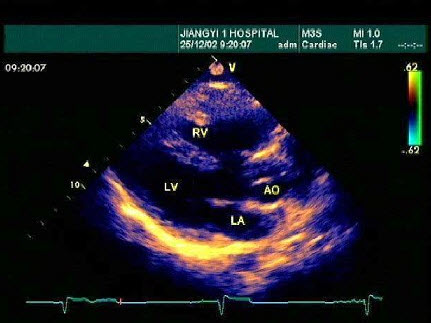

96、单项选择题

某患者左室长轴切面超声心动图如图所示,诊断为()

A.正常声像图

B.扩张型心肌病

C.房间隔缺损

D.室间隔缺损

E.三尖瓣返流